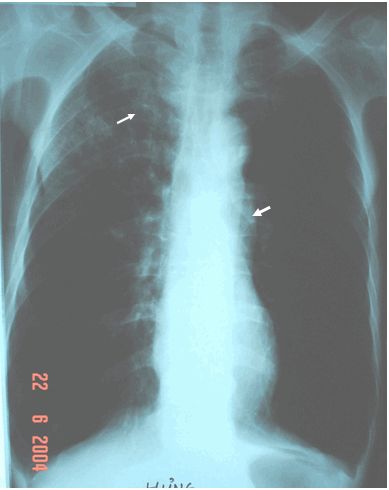

Hội chứng Pierre Marie trên Xquang

Hội chứng Pierre Marie: hội chứng này gặp trong bất kỳ loại K biểu mô tế bào nào, nhưng hay gặp nhất trong K biểu mô tế bào vảy, K biểu mô tuyến & ít gặp nhất trong K biểu mô tế bào nhỏ.

- Hình ảnh xương khớp phì đại (hypertrophic osteoarthropathy): Tỷ lệ gặp khoảng 5% bệnh nhân K phổi loại biểu mô không phải tế bào nhỏ, biểu hiện bằng:

- Đau khớp với tính chất đau không đối xứng (các khớp hay bị như cổ chân, cổ tay & đầu gối), dày màng xương dài & u phổi.